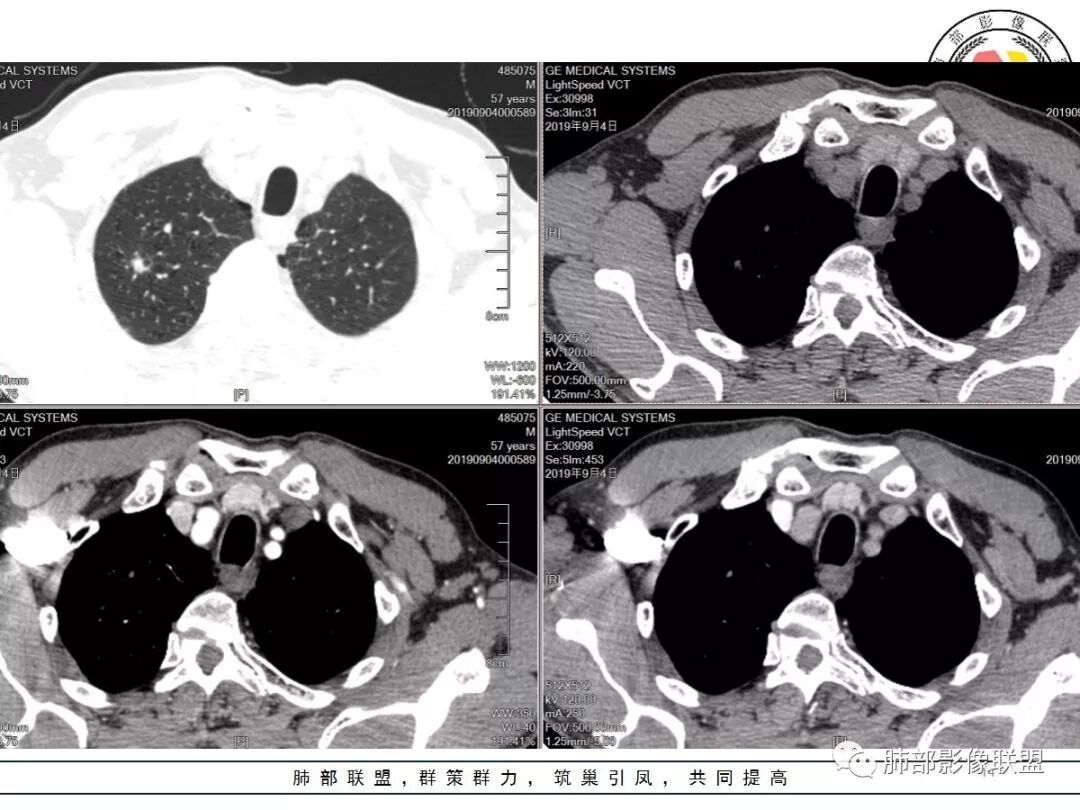

男,57岁,因“体检发现右上肺占位”入院。凝血常规、血常规、肾功能等均未见明显异常。

CT值:

平扫  18                          动脉期  28                      静脉期 41

双肺尖斑片状影及结节影,边缘平直为主,边缘可见胸膜牵拉,考虑结核,鉴别诊断腺癌,本病特点,多灶性,多态性,胸膜牵拉线纤细。

右上肺病灶,边缘平直,有卫星灶,强化不明显,考虑结核可能大

结核。右上肺结节密度均匀轻度强化,结节边缘清晰有小分叶,周围细长软毛刺,有卫星灶。左上肺近纵隔类似片状结节。

右肺尖结节边缘可见卫星灶,结节边缘平直凹陷、长毛刺,外观上有炎性结节的特点

增强扫描右肺尖结节强化不明确,但左肺尖后段结节出现了典型的环形强化

右肺上叶结节灶,边缘膨隆,有毛刺,胸膜牵拉,轻度强化,左肺上叶结节灶环形强化,左肺考虑结核,右肺结节灶,不排除疤痕癌。

两肺上叶结节影,右肺结节边缘清晰,平直,有胸模牵拉,有卫星灶,强化不明显,左肺结节周边强化,两肺门淋巴结肿大,整体考虑结核。

中老年男性,体检发现双肺尖结节,边缘长索条,邻近胸膜粘连,病灶收缩力不太强,右肺尖病变周围少许卫星灶,增强后环形强化表现,首先考虑结核,治疗后复查

两上肺(右尖左尖后)都有小结节影,右肺尖结节边缘可见卫星灶,结节边缘平直凹陷、长毛刺,部分膨隆,增强扫描右肺尖结节强化不明确;左肺尖后段结节边缘平直凹陷,增强见环形强化。考虑结核可能性大,右上肺注意鉴别腺癌。

老年男性,体检发现右上尖段及左上尖后段不规则结节影,右上尖段结节边缘长毛刺、似见卫星灶、局部胸膜牵拉,增强无明显强化。左上结节环形强化,考虑结核。老年男性,肺气肿背景,注意排除右上肺腺癌。

右肺上叶尖段结节,边缘平直收缩,周围有细长毛刺,有卫星灶,符合结核,但有静脉期轻度强化,结核应该没有强化,肺癌?

双肺尖结节 左肺边缘收缩 环形强化 右肺病灶上部边缘平直及长毛刺 下部分边缘膨隆及分叶 细短毛刺 好像有局灶强化 不除外结核基础上的瘢痕癌可能

倾向二元,左肺上叶病灶环形强化支持结核,右肺上叶结节平直、部分稍膨隆,胸膜牵拉征,部分毛刺粗短、支气管似乎边缘截断,临近小叶间隔增厚,延迟强化,密度似乎不均匀,内见小点状坏死,腺癌放前面,炎性放待排。

老年男性,体检发现,右肺上叶尖段类圆形结节

小叶中心型肺气肿背景,一般提示吸烟

周围有类似小结节

根据周围常规:我们要考虑结核的可能

我们再看右肺上叶这个较大病灶主体

类圆形,浅分叶

胸膜凹陷

血管纠集

局部凸起

强化幅度超过20HU

边缘平直